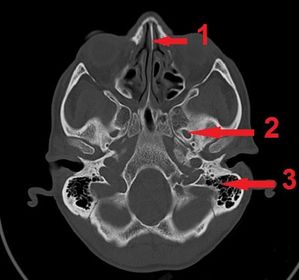

1) identify 1,3 2) mention structure pass through 2 1) 1- nasal septum 3- mastoid air sinus 2) mandibular nerve